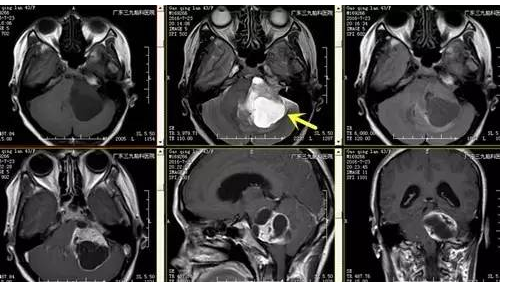

高女士,43岁,头痛伴行走不稳,伴轻度面瘫1月余入院,行颅脑CT及MR示颅内占位肿物51.4mm×38.6mm×40.4mm,其内可见大小不等囊变,增强后囊壁及肿块实质部分可见明显强化,肿块与左侧内听道关系密切,左侧内听道扩大,脑干受压右移,诊断:左侧桥小脑脚区占位性病变。